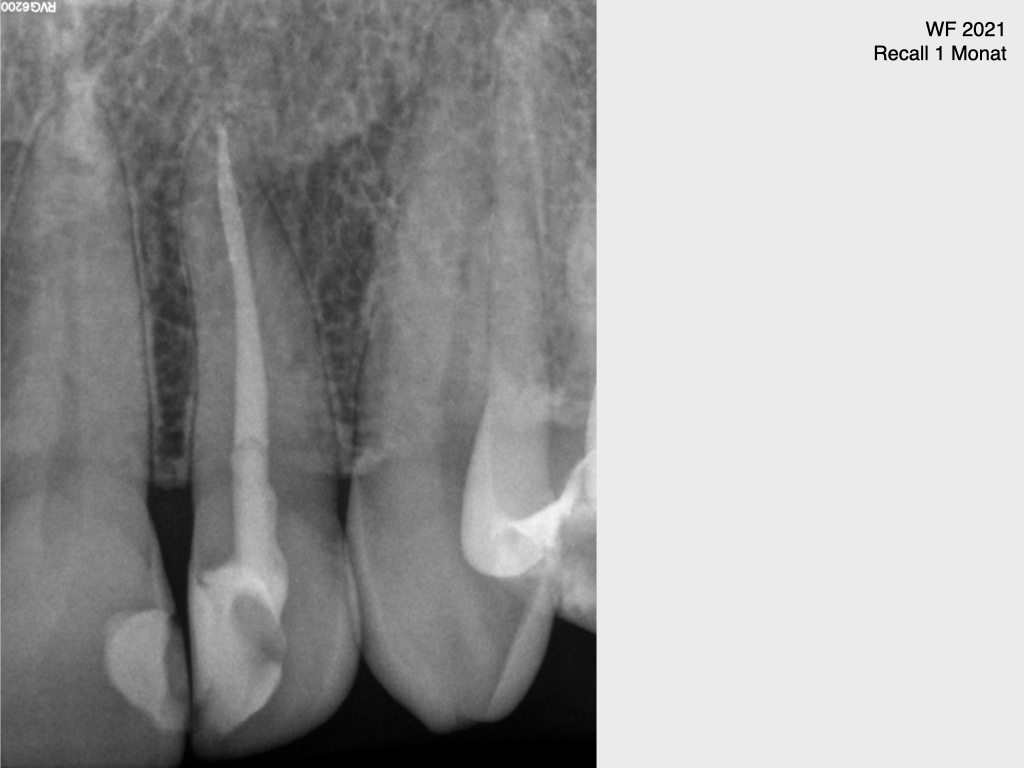

10039.006

13. Dezember 2021

1024 × 768

Frontzahn 22 (3)